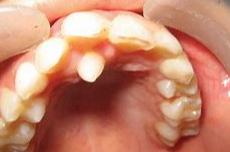

如果多生牙不仅长了,还占了正常牙的地儿,被挤走的正常牙就只好自寻出路了,靠近嘴唇这侧还挺宽敞,那就往这里长吧,小歪牙就出现了。

在婴幼儿期,家长要多注意,如果发现额外牙,及时看医生。换牙时期也更要注意孩子牙齿变化,不干预的话多生牙可能影响恒牙萌出或造成牙齿畸形。